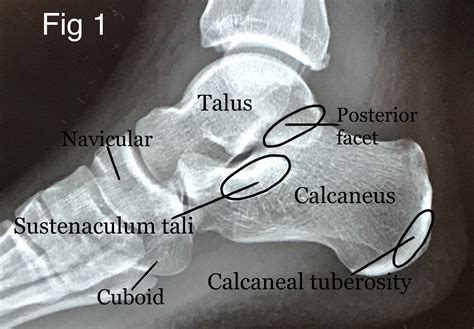

A Calcaneus X Ray is a medical imaging technique used to visualize the calcaneus, or heel bone. This type of X-ray is particularly useful for diagnosing fractures, dislocations, and other abnormalities in the heel area. The calcaneus is the largest bone in the foot and is subject to significant stress and impact, making it prone to injuries, especially in athletes and individuals involved in high-impact activities.

Interpreting the results of a Calcaneus X Ray requires the expertise of a radiologist or orthopedic specialist. The images are carefully examined for signs of fractures, dislocations, or other abnormalities. Here are some common findings that may be identified:

• Fractures: These can range from simple cracks to complex fractures involving multiple bone fragments. The location and severity of the fracture will determine the appropriate treatment.

• Dislocations: These occur when the bones in the heel area are displaced from their normal position. Dislocations can cause significant pain and may require surgical intervention.

• Bone Spurs: These are bony projections that can form on the heel bone due to chronic stress or inflammation. Bone spurs can cause pain and discomfort, especially during weight-bearing activities.

• Arthritis: X-rays can also reveal signs of arthritis, such as joint space narrowing and bone spurs, which can affect the heel and surrounding joints.

• calcaneus x ray anatomy